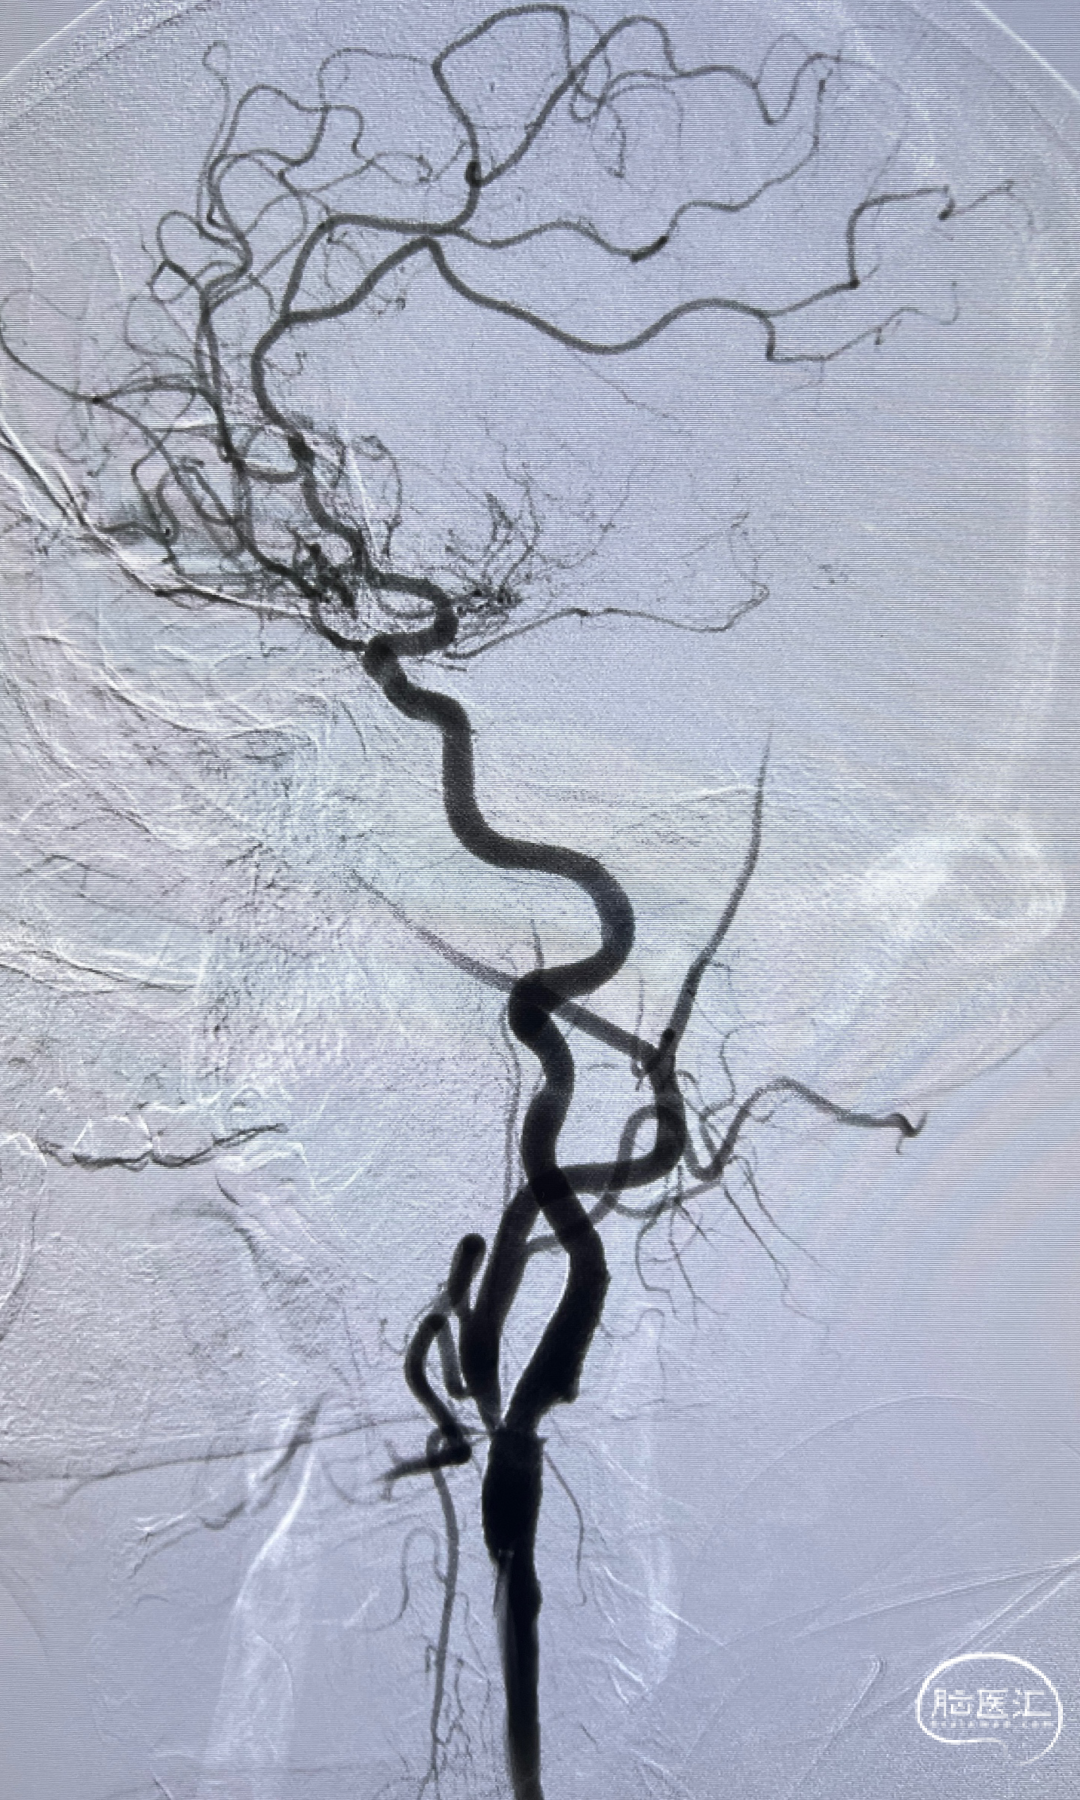

左侧颈内动脉重度狭窄,左侧大脑中动脉闭塞,通过前交通动脉向右侧大脑中动脉供血区代偿。

狭窄程度:75%,狭窄长度:16mm

狭窄近端参考血管直径:7.60mm

狭窄远端参考血管直径:6.20 mm

左侧颈内动脉正侧位造影,狭窄解除。